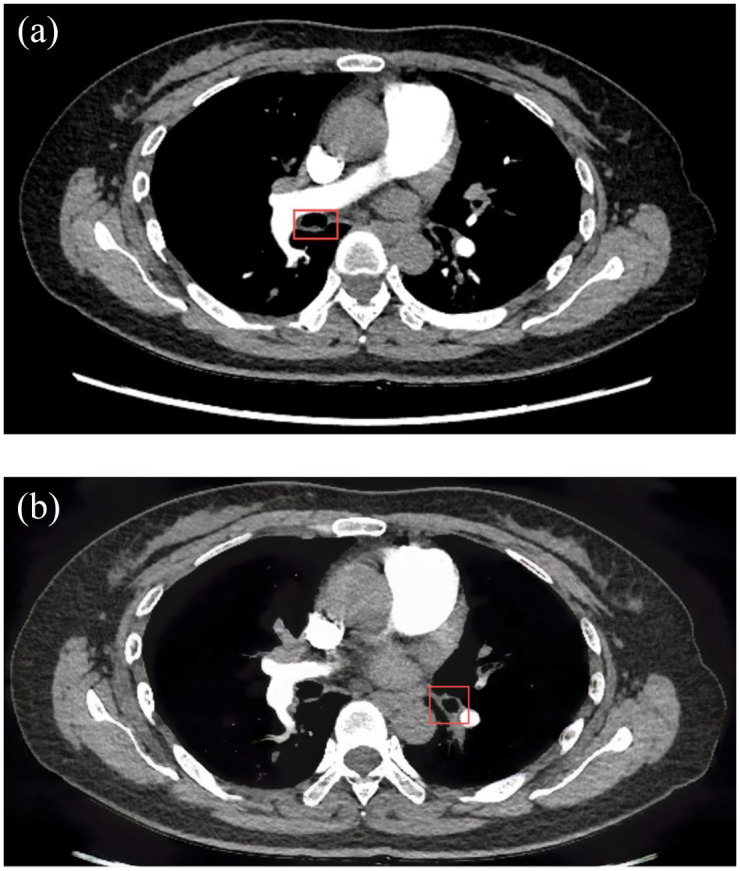

We report a case of tracheobronchial amyloidosis (TBA) in a 55-year-old woman with newly diagnosed primary Sjögren's syndrome (SS), presenting with persistent cough, hemoptysis, and dry mucosal symptoms. Chest CT showed thickened airway walls and cystic lung changes, while bronchoscopy revealed nodular lesions with exposed vessels. Congo red staining confirmed amyloid deposition with κ light-chain dominance, consistent with AL amyloidosis. Despite immunosuppressive therapy, airway lesions persisted, highlighting the challenge of managing localized amyloidosis in SS. This case underscores the need for early recognition of TBA in SS patients presenting with respiratory symptoms.